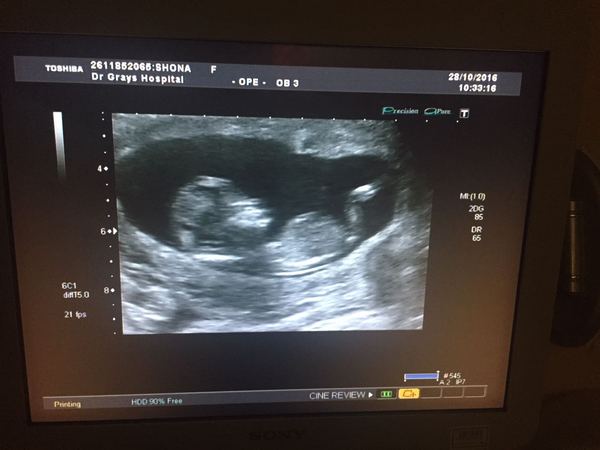

Shoney85 · 10/11/2016 06:56

Hi everyone I'm the newbie, currently 14+5, due may 6th. Attached my scan photo. This is our first baby. Very nervous. Had a wee scare at the start and sooo worried but we are here and still scared something will happen. Soooo excited, can't wait to meet him/her. My tiredness is starting to go, getting my energy back however still suffering with nausea and sickness, my actual sickness didn't start till about 10/11 and has gotten worse, been tough but trying to get through is as I know the result will be awesome xx

teainbed · 10/11/2016 07:08

Hi Shoney and welcome.

There's identifying details on your scan pic like your CHI number, did you realise? If you want it removed you can report your own post to MNHQ.